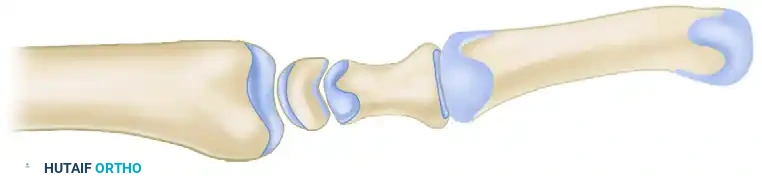

Biomechanics and Optimal Joint Positioning

The success of a TMC arthrodesis hinges entirely on achieving the correct three-dimensional spatial orientation of the thumb. Improper positioning leads to severe functional deficits, such as the inability to place the hand flat on a surface or the inability to perform a functional pinch.

Surgical Pearl: The "Fist and Flat" Rule

The ideal position for TMC arthrodesis is approximately 40 to 45 degrees of palmar abduction, 30 degrees of radial abduction, and 15 degrees of pronation. Clinically, this means the thumb pulp should comfortably oppose the index and middle fingers, and when the hand is held in a tight fist, the thumb should overlie the dorsum of the middle phalanx of the index finger. Furthermore, the patient must be able to lay their palm completely flat on a table.